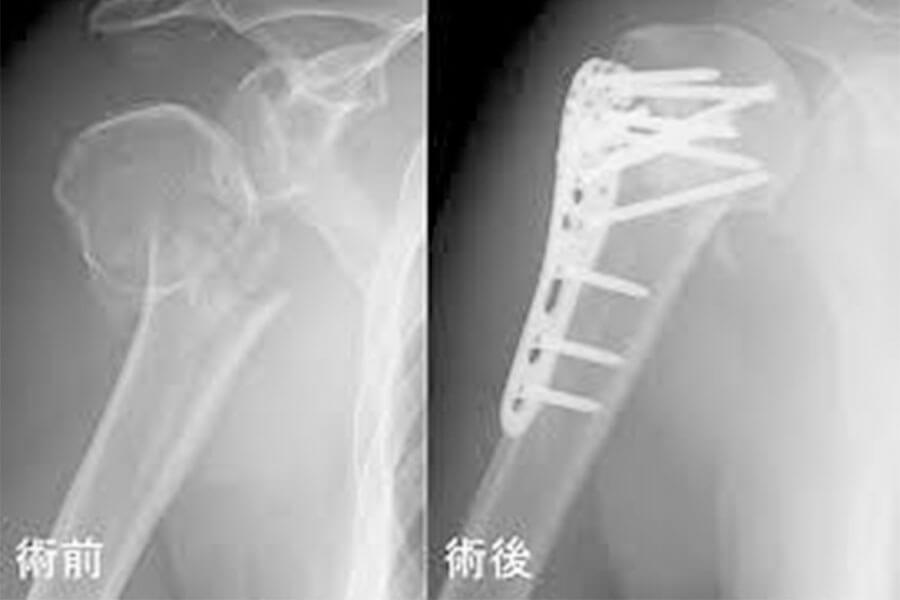

上腕骨骨折